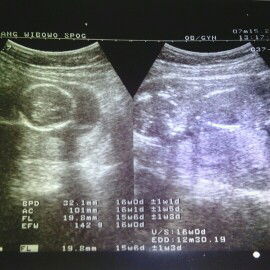

hasil usg

Bun , usia janin saya 16 minggu ,, kira kira ukuran segini janin saya tinggi nggak ?